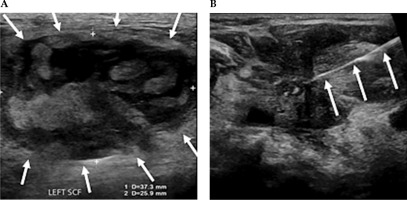

Fig. 4

A) Ultrasound demonstrating measurements of a large partially solid-cystic mass of lymph nodes in the left supraclavicular fossa (SCF). B) A fine needle aspiration was subsequently performed. Cytology results confirmed metastatic squamous cell carcinoma. A 25 G needle is delineated entering the left SCF lesion, whilst performing a fine needle aspiration